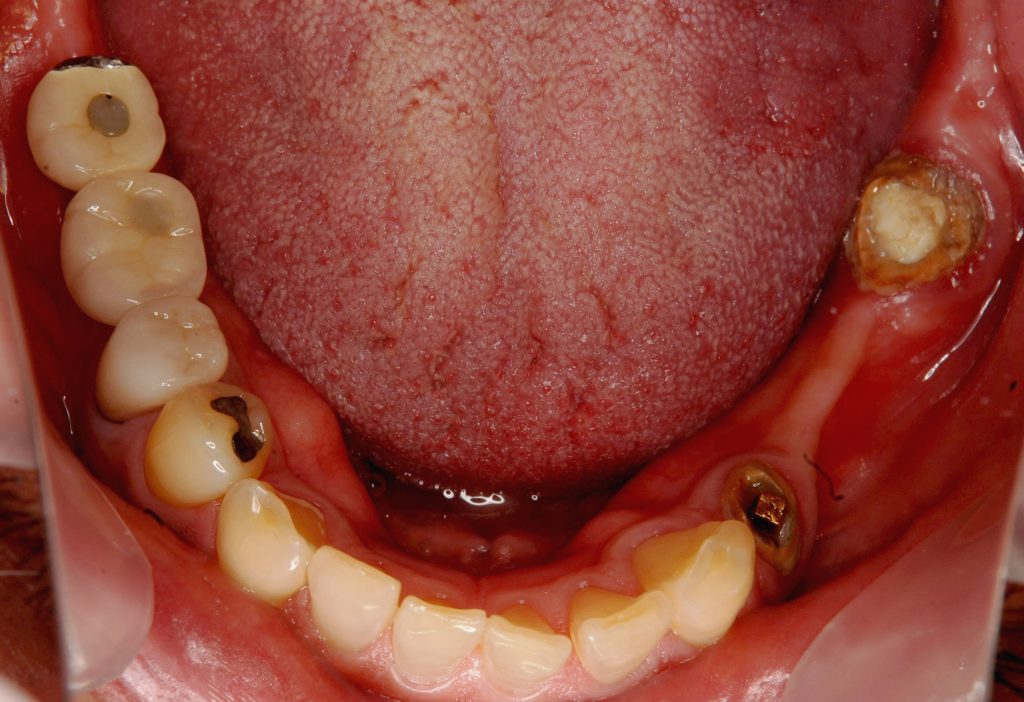

症例240代 女性 主訴 義歯が動いて煩わしい

治療前

治療後

入れ歯だと奥歯しっかり噛めず、取り外しも煩わしいので固定制のインプラントにして欲しいと訴え来院。

左右大臼歯部は、残存骨が1~2㎜程度で骨高が不足している為、ソケットリフト(上顎洞洞底膜挙上術)を行い、インプラントを埋入。口腔内全体で7本のインプラントを埋入。

約4ヶ月の治療期間を経て、全てジルコニアを装着し終了。

リスクとしては外科的侵襲がある。デメリットは、保険外診療の為、経済的負担がある。

費用 381万(税込)(オペ・仮歯・最終補綴物まで含む)